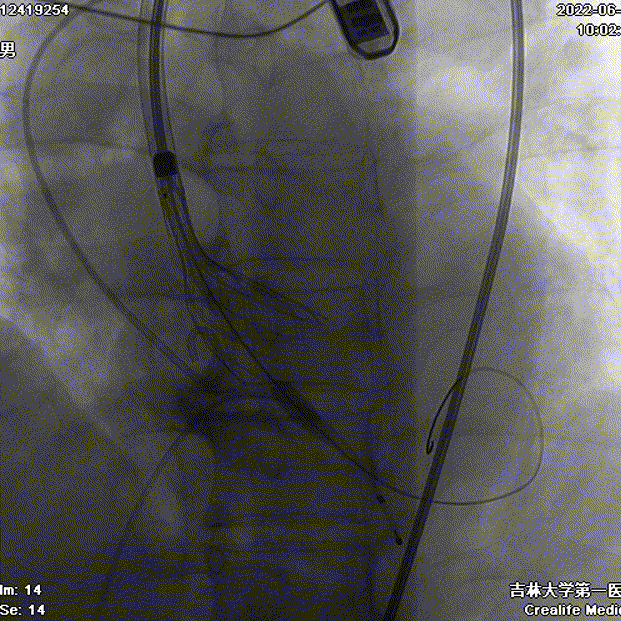

术中影像

23mm球囊预扩张

瓣膜工作位造影

瓣膜形态良好 位置理想

少量瓣周漏 平均跨瓣压差7mmHg